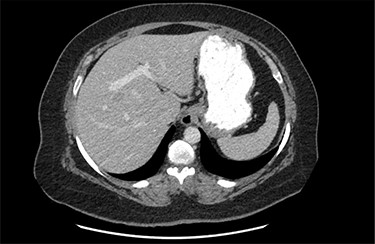

On assessment, the patient denied any symptoms related to her neuroendocrine tumor, including flushing, increased sweating, increased heart rate, wheezing, shortness of breath, diarrhea, weight loss or appetite changes. The only significant family history was a paternal and maternal grandfather with colon cancer. Imaging results were significant for computed tomography (CT) of chest demonstrating very small, but multiple, pulmonary nodules. A CT abdomen and pelvis demonstrated the known neuroendocrine tumor near the ileocecal valve (Fig. 1) as well as two poorly visualized liver lesions (Figs 2–4). The magnetic resonance imaging (MRI) demonstrated two separate one-centimeter lesions in segment 5 and 7 of the liver (Figs 5 and 6). The portal vein lacked normal left and right bifurcation; there was a circumferential right portal vein, which coursed anteriorly and superiorly and ultimately to the left lobe of the liver.